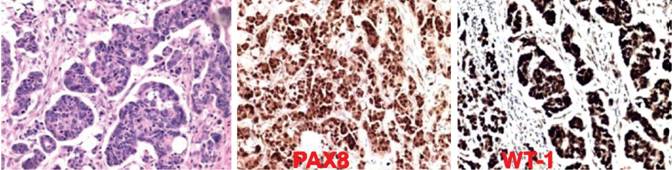

A 64-year-old Brazilian woman was admitted on January 24th 2016 because of abdominal distension causing progressive breathlessness with two months of duration. She had noticed changes in her bowel function, with alternate constipation and diarrhea. Before admission, a chest radiography showed bilateral pleural effusion; and abdominal computed tomography revealed an extensive hypogastric mass with central areas of necrosis and involving adjacent small and large intestinal bowels. In addition, there was massive ascites, and infra diaphragmatic bilateral lymph node enlargement (Figure 1). On admission, she claimed abdominal pain and presented with tachycardia and dyspnea. Physical examination revealed BMI: 29 kg/m2, normal heart function, pleural effusion and ascites, absence of visceromegaly and of lymph node changes, or peripheral edema. Diagnostic thoracentesis and paracentesis were done with suspicion of Meigs’ syndrome. Pleural fluid was a transudate and malignant cells were not observed in pleural specimens, whereas ascites was clearly carcinomatous. Routine tests showed: hemoglobin 13.7 g/L, hematocrit 42.1%, leukocytes 5.18 × 109/L, platelets 476 × 109/L, urea 12.7 mg/dL, creatinine 0.6 mg/dL, AST 55.4 U/mL, ALT 37.5 U/mL, ESR 61/1ah, C-reactive protein 5 mg/dL; the rest of biochemistry was normal. Worthy of note was the elevated level of CA 125: 6,973.0 U/mL (reference: < 35 U/mL). Pulmonary computed tomography angiography ruled out lung thromboembolism, and showed bilateral pleural effusion. PET-CT scan detected hypermetabolic foci indicative of neoplastic involvement in the hypogastric mass, in abdominal and thoracic lymph nodes, and in the first left rib; in addition to smooth and nodular inspissation in some peritoneal and pleural locations. Exploratory laparotomy revealed a large hypogastric tumor (9.9 cm x 9.7 cm x 7.4 cm) without plans of cleavage, and omental caking that indicated peritoneal carcinomatosis. Histopathology findings from samples obtained of the peritoneum as well as of the tumor were consistent with the diagnosis of HGSOC (Figure 2). Immunohistochemistry: cytokeratins 40, 48, 50 and 50.6 kDa (AE1/AE3) positive; estrogen receptor (SP1) positive; PAX8, transcription factor of the family of gene-paired box [PAX] (MRQ50) positive; and product of oncogene Wilms Tumor 1 [WT-1] (6F-H2) positive. Additionally, the CDX2, intestinal transcription factor (EPR2764Y) and TTF-1, thyroid and lung transcription factor (clone 8G7G3/1) were all negative. The possibility of surgical approach was discarded. Therefore, patient was referred to outpatient Oncology care, and underwent chemotherapy with paclitaxel and carboplatin. It is worth noting that the patient’s general condition as well as ascites and hydrothorax had progressively improved on the course of chemotherapy. Therefore, the patient did not undergo further thoracentesis since her hospital discharge. Currently, approximately 10 months after beginning of specialized follow-up, no recurrence of ascites or significant pleural effusion was revealed by routine radiographic control (Figure 3).

Figure 2: Immunohistochemistry evaluation strongly consistent with diagnosis of high-grade ovarian serous carcinoma, revealing the expressions of PAX8 and WT-1; the cytokeratins 40, 48, 50 and 50.6 kDa (AE1/AE3) and the estrogen receptor (SP1) were also found positive.

Initially, the patient of the present case study had the diagnostic hypothesis of MS, but the diagnosis of pseudo-MS was confirmed with base on histopathology findings.1-6 The classical triad of MS specifically refers to a benign ovarian tumor associated with hydrothorax and ascites.1-6 Moreover, these cavity effusions should resolve after tumor removal;1-6 phenomenon not found in people with carcinomatous ascites.9 Although the ovarian tumors represent the fifth cause of death by cancer in women, they are the most lethal gynecologic malignancies in the US.10 The morphological and phenotypic patterns of this tumor include HGSOC and low-grade serous cancer, endometrioid, clear cell and mucinous carcinoma.10 Furthermore, the HGSOC may be genetically classified in the following molecular groups: immunoreactive, proliferative, differentiated, and mesenchymal.10 Useful protein markers are PAX8 and WT1.10 The main ovarian tumors related to MS are fibroma, thecoma, Brenner’s tumor, granulose cell tumor, and teratoma.4-6 Pseudo-MS is associated with other benign or malignant pelvic tumors, and pseudo pseudo-MS is due to systemic lupus erythematosus.2,3,6 The mechanisms of the elevated levels of CA 125 in patients with active systemic lupus are related to serositis, inflammatory phenomena involving proinflammatory cytokines, and the expression of this tumor marker by cells of the omentum and mesovarium.3 Histopathology data of biopsy samples showed peritoneal carcinomatosis in our patient. A major concern in the present case was the possibility of pseudo-MS due to metastases of digestive tract cancers with high levels of CA 125, as reported in two women with colon cancer (1,150.0 U/L)3 and omental caking by pancreatic cancer (465.0 U/L).9 Concerns about the origin of the pelvic mass were ruled out by immunohistochemistry confirmatory findings of pseudo-MS secondary to a HGSOC. Cytokeratins 40, 48, 50 and 50.6 kDa (AE1/AE3) and estrogen receptor (SP1) positive, and the expression of PAX8, and of WT-1 were consistent with ovarian etiology.10 Pretreatment levels of CA 125 higher than 500 U/ml in patients with HGSOC of FIGO stage III were found in association with enhanced survival rate.5 The woman herein reported presented with exceeding high blood level of CA 125 (6,973.0 U/mL); the presence of ascites and omental caking discarded possibilities of surgical approach. The antigen CA-125 is a glycoprotein that origins in the epithelium of fallopian tubes, endometrium, mesothelium of the pleura, peritoneum, and pericardium.6,7 High levels of this protein marker may be found in menstruation period, pregnancy, endometriosis, peritonitis, or liver cirrhosis.7 Finally, etiopathogeny of cavitary effusions both of MS and of pseudo-MS merit comments. The mechanisms of ascites and pleural effusion in Meigs’ syndrome are controversial.6-8 Hypotheses include passage of ascites through diaphragmatic foramens or lymphatics, and increased capillary permeability by VEGF or inflammatory cytokines.6-8 Whereas pleural transudates may be due to local changes in hydrostatic or oncotic pressures; exudative effusions often occur in MS, and are found in the vast majority of the pseudo-MS cases.6-8 Worthy of note, novel HGSOC cell models can reliably generate tumors and ascites,10 findings that may contribute to better understanding about these syndromes.